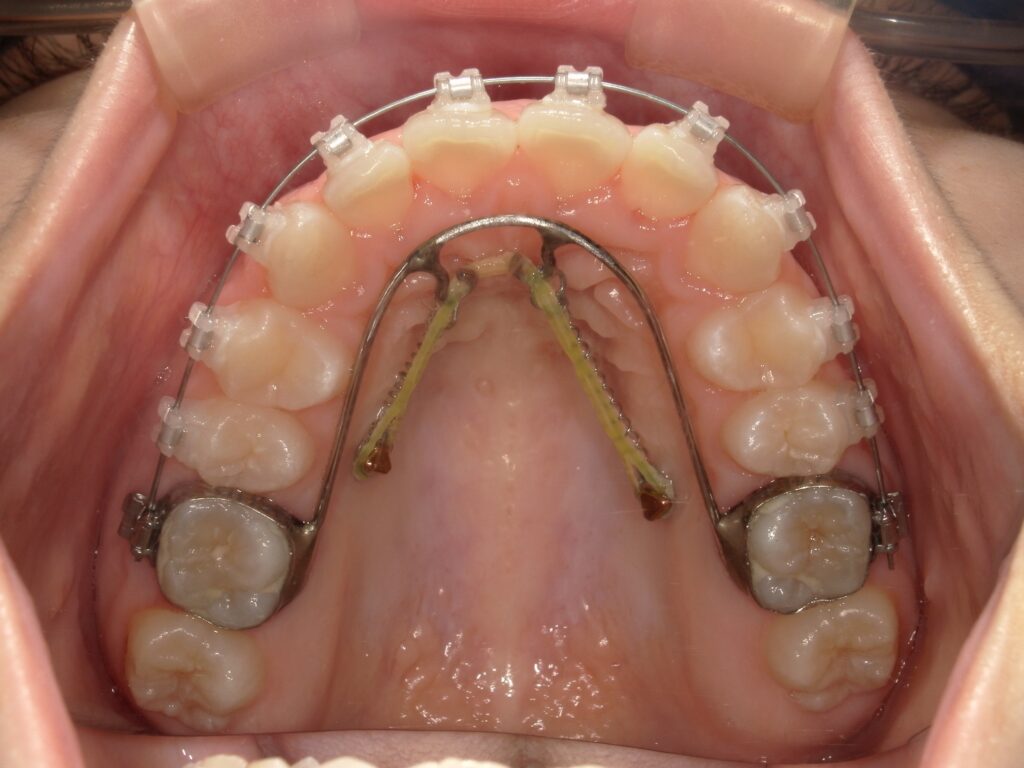

アンカースクリューとは、歯科矯正治療において使用される小型のチタン製のネジです。直径は約1〜2mm、長さは6〜10mm程度で、口腔内の骨に一時的に埋め込まれます。写真では、上顎の真ん中に打ちこまれています。